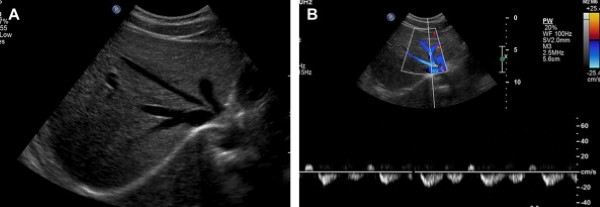

Tăng Chu chuyển vòng (Increased phasicity)

Sóng Doppler bình thường của tĩnh mạch cửa không đập theo nhịp tim; sóng có dạng phổ đập mạnh hay có hai vòng trong mỗi chu chuyển chênh nhau rõ ở dòng chảy tĩnh mạch cửa là một dấu hiệu thường gặp trong suy tim phải (Hình 5) [11,12]. Siêu âm gan thường được chỉ định ở các bệnh nhân suy tim phải bởi vì các chỉ số xét nghiệm chức năng gan tăng do sung huyết gan thụ động. Tĩnh mạch chủ dưới và các tĩnh mạch gan bị giãn là một dấu hiệu quan trọng để chẩn đoán suy tim phải ứ máu ở gan. Sóng phổ đập mạnh của tĩnh mạch cửa có liên quan với áp lực nhĩ phải tăng, đặc biệt trong các trường hợp hở van ba lá, tăng áp lực động mạch phổi nặng, tràn dịch màng ngoài tim nhiều, khối u nhĩ phải, và viêm ngoại tâm mạc co thắt [13].

Tăng nhẹ chu chuyển vòng còn được quan sát thấy ở các trường hợp rò giữa tĩnh mạch cửa và tĩnh mạch gan, và các nối tắt cửa-chủ [13].

Hình 5. Dòng chảy hai chu chuyển vòng ở tĩnh mạch cửa bệnh nhân nữ 59 tuổi có tiền sử suy tim phải và viêm gan C. (Hình A) Ảnh siêu âm Doppler màu chứng minh dòng chảy hai chu chuyển vòng trong tĩnh mạch cửa, sóng kéo dài ở trên và dưới đường cơ bản. (Hình B) Ảnh siêu âm thang xám phát hiện các tĩnh mạch gan giãn to đổ về tĩnh mạch chủ dưới cũng bị giãn (các mũi tên) do suy tim phải và tăng thể tích tuần hoàn. (Hình C) Sóng mạch đập mạnh ở bên trong tĩnh mạch gan giữa.